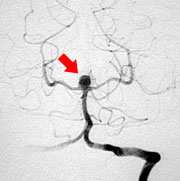

脳動脈瘤手術

脳動脈の瘤(動脈瘤)(図3)はある日突然破裂し、くも膜下出血を発症します。くも膜下出血は全体のおよそ30%が亡くなってしまう予後不良な病気です。症状は突然の激しい頭痛で通常嘔吐も伴います。

脳動脈瘤の治療は開頭術による脳動脈瘤頚部クリッピング術と血管内手術による脳動脈瘤塞栓術がありますが、現状ではクリッピング術が主流です。当科では破裂脳動脈瘤はもちろんのこと未破裂脳動脈瘤に対しても積極的に外科的治療を行っています。手術を行うにあたっては安全にかつ、確実に手術を行うことが是大前提です。そこで当科では以下にのべる工夫を行い、手術合併症を限りなくゼロになるように日々努力しています。